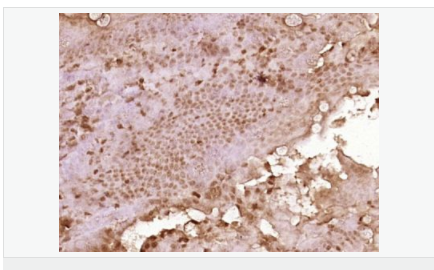

| 產(chǎn)品應(yīng)用 | WB=1:500-2000 ELISA=1:5000-10000 IHC-P=1:100-500 IHC-F=1:100-500 ICC=1:100-500 IF=1:100-500 (石蠟切片需做抗原修復(fù)) not yet tested in other applications. optimal dilutions/concentrations should be determined by the end user. |

| 細胞定位 | 細胞漿 |

| 產(chǎn)品介紹 | C3orf32 (chromosome 3 open reading frame 32), also known as fls485, is a 353 amino acid protein encoded by a gene that maps to human chromosome 3p26.1. Chromosome 3 is made up of approximately 214 million bases encoding over 1,100 genes. Notably, there is a chemokine receptor gene cluster and a variety of human cancer related loci on chromosome 3. Particular regions of the chromosome 3 short arm are deleted in many types of cancer cells. Key tumor suppressing genes on chromosome 3 encode apoptosis mediator RASSF1, cell migration regulator HYAL1 and angiogenesis suppressor SEMA3B. Marfan Syndrome, porphyria, von Hippel-Lindau syndrome, osteogenesis imperfecta and Charcot-Marie-Tooth disease are a few of the numerous genetic diseases associated with chromosome 3. Subcellular Location: Cytoplasm. Tissue Specificity: Expressed in enterocytes of small and large intestinal mucosa (at protein level). Expressed in enterocytes, chromaffine and interstitial cells. SWISS: Q9Y2M2 Gene ID: 51066 Database links: Entrez Gene: 51066 Human SwissProt: Q9Y2M2 Human Unigene: 561182 Human Unigene: 740735 Human Important Note: This product as supplied is intended for research use only, not for use in human, therapeutic or diagnostic applications. |